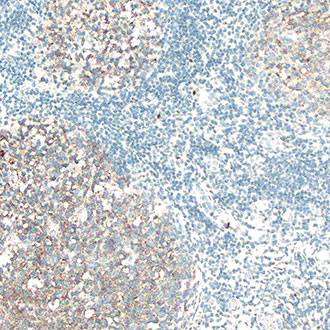

CD5

CD5 -